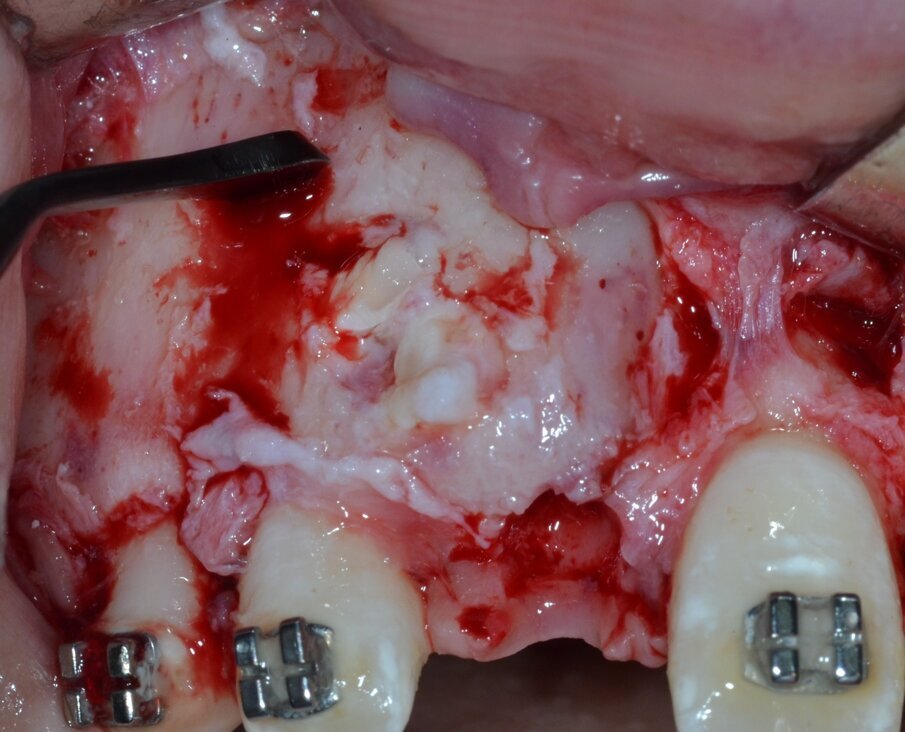

La neoformazione viene aggredita in due tempi operatori distinti: il primo tempo consiste nell’ostectomia per erosione della corticale ossea che la ricopre integralmente (Fig. 6) e, successivamente, viene effettuata un’osteotomia perilesionale alla ricerca del piano di clivaggio tra la neoformazione e il tessuto osseo circostante (Fig. 7).

Fig. 6_Ostectomia per erosione della corticale ossea.

Fig. 7_Osteotomia perilesionale che segue il contorno della neoformazione.